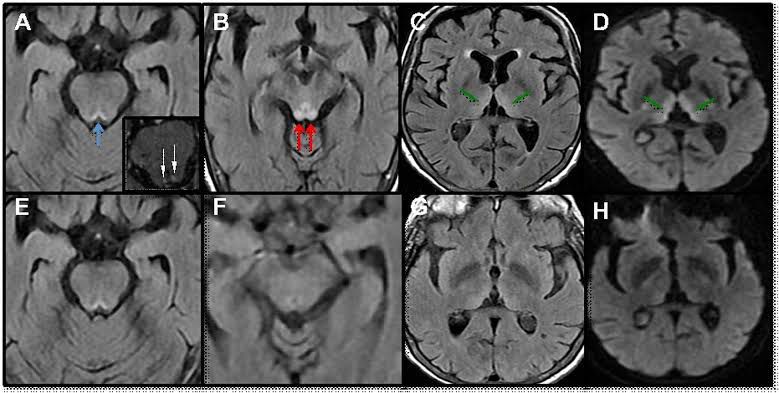

Wernicke's encephalopathy is a degenerative brain disorder caused by the lack of thiamine (vitamin B1). It may result from alcohol abuse, dietary deficiencies, prolonged vomiting, eating disorders, or the effects of chemotherapy. B1 deficiency causes damage to the brain's thalamus and hypothalamus.